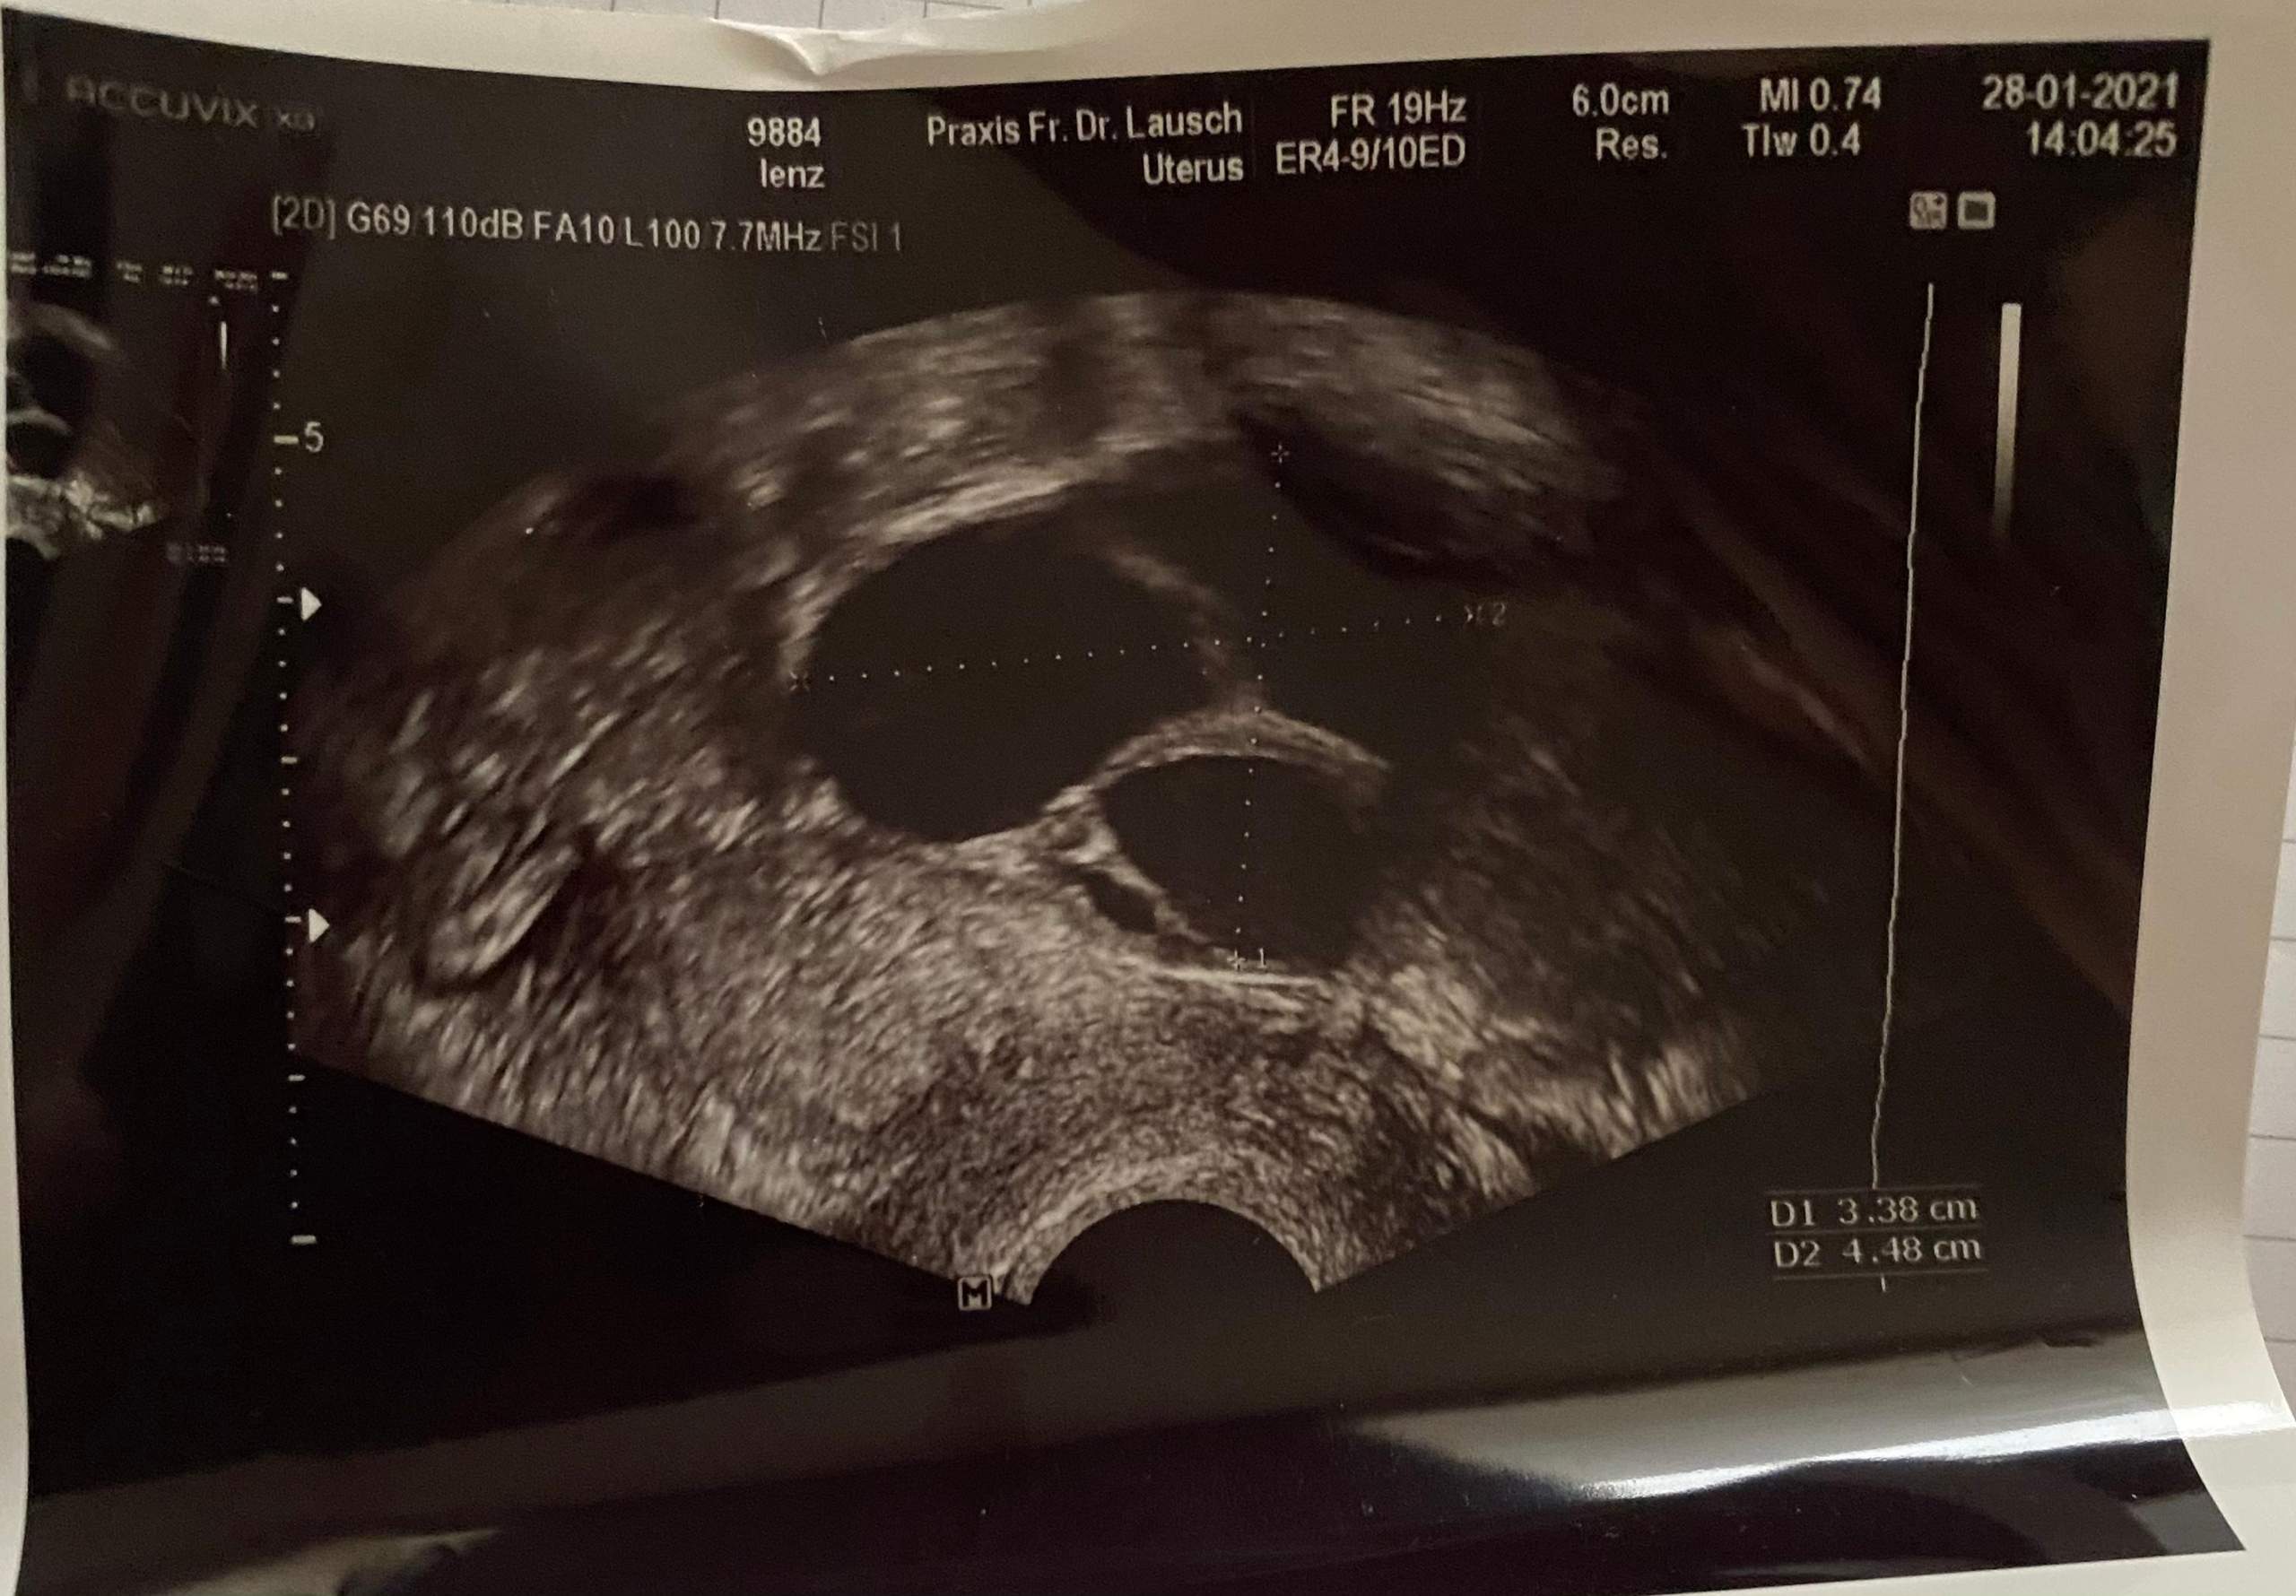

Zystischer Tumor Sonographieatlas Erlangen

Ovarien Sonographieatlas Erlangen